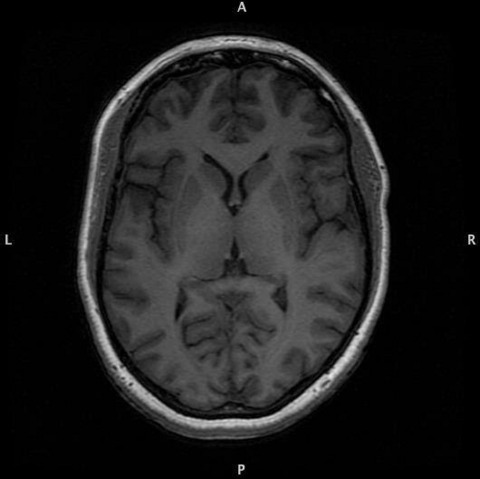

I came across these during a harddrive cleanup. I haven't seen these in a while. Ladies and gentlebeings, my brain. Sometimes I wonder if I should be saddened by the disturbing amount of symmetry, or relieved.

I got them as part of a psych study I volunteered for many years ago.

Brain MRI Brain MRI